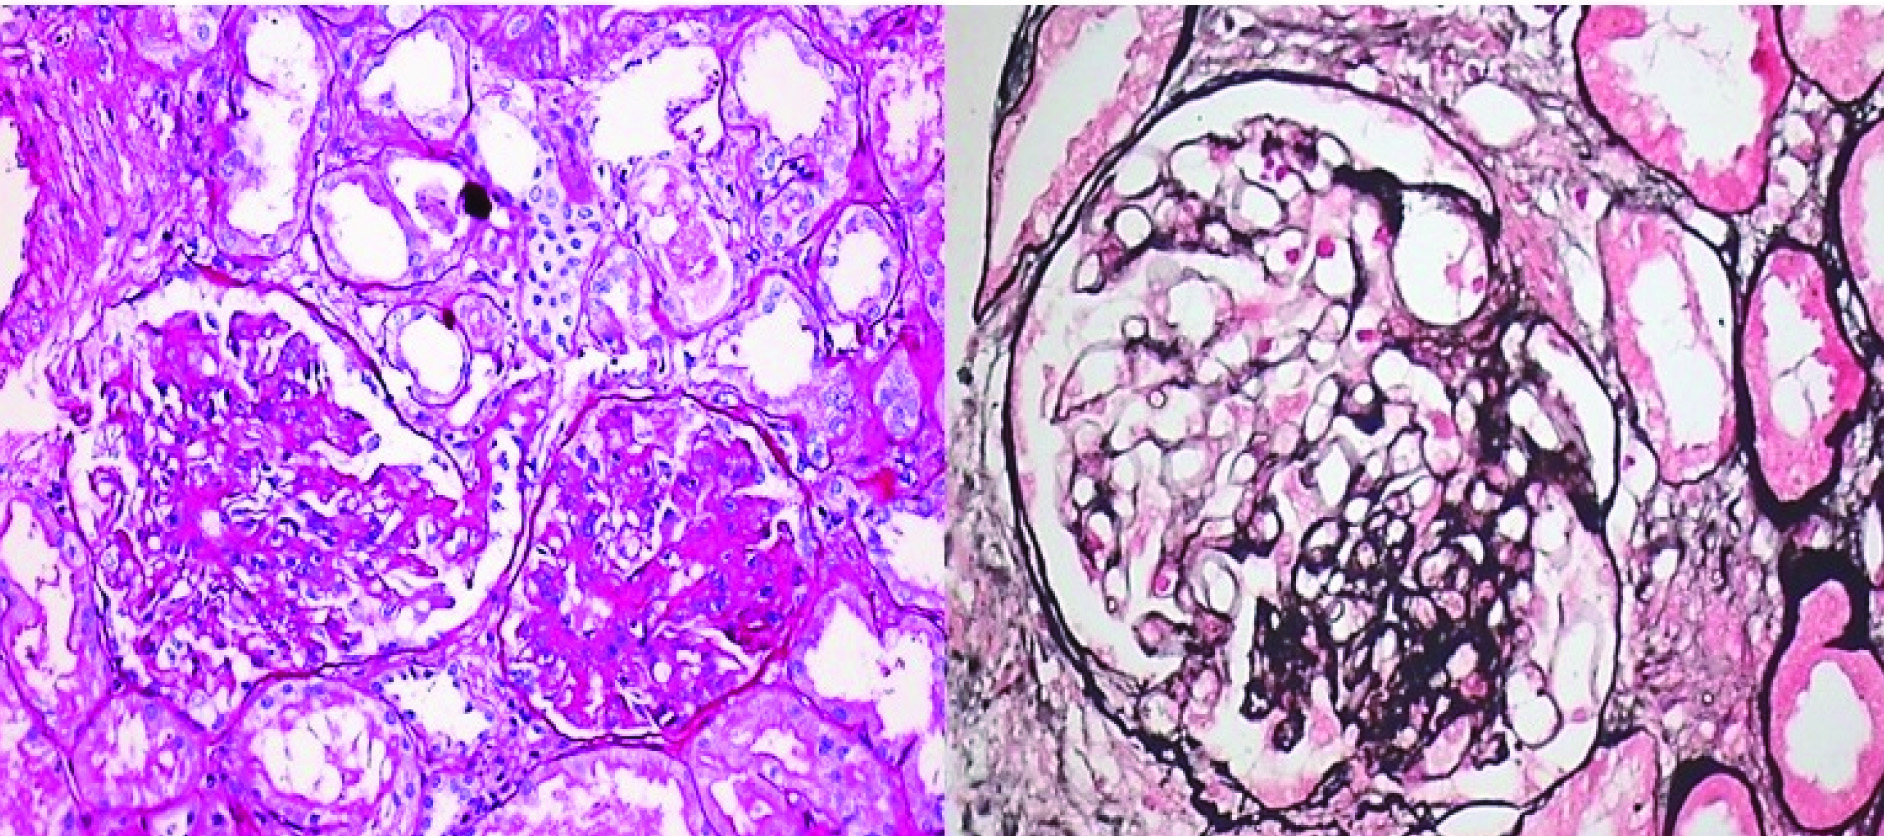

Not otherwise specified (NOS) or classical variant: Focal and segmental consolidation of capillary tuft by increased extracellular matrix, obliterating the glomerular capillary lumen with or without podocyte hyperplasia. Excluding other morphological variants [Table/Fig-2a,b]

Classical (NOS) variant of FSGS: a) PAS 20X; b) Jone’s methanamine silver 40X. (Images from left to right)